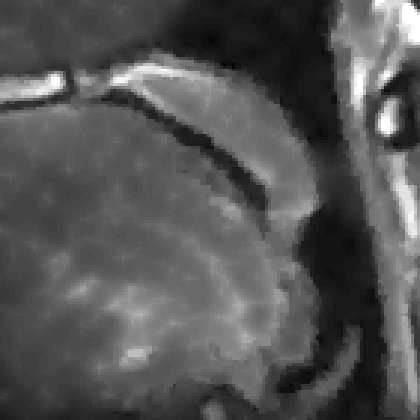

We display the noisy image and the reconstructed images from these three denoising methods in Fig. 8 111 Image retrieved from http://radiopaedia.org/ by Frank Gaillard.. To better understand the performance, we zoom in the selected part of the image and display them in Fig. 9.

Refer to caption

(a) Noisy

(b) Anisotropic TV

(c) TFV, α=1.3𝛼1.3\alpha=1.3

(d) TV-TFV, α=1.3𝛼1.3\alpha=1.3

Figure 8: Denoising results for models with different regularities. Here α𝛼\alpha denotes the fractional order of derivative in TFV model.

We observe that the anisotropic TV suffers from the staircase artifact due to the fact that the TV is local operator. On the other hand, the reconstruction with TFV regularity has blurry effect on the edges. This is not surprising because the TFV is a non-local method and it is less edge sensitive than TV. Instead, the TV-TFV regularity avoids such artifacts and has a better reconstruction of both the edges and the overall image.

We also present the numerical results of different performance measurements in Table 3. The TV-TFV regularity shows better results in such measurements as well.

Table 3: Numerical results for denoising with different regularities.

\hlineB3 Model psnr snr rela_err

\hlineB3 Noisy 20.9199 6.0853 0.3914

TV 31.0007 16.1661 0.1226

TFV 31.6910 16.8565 0.1133

TV-TFV 32.1948 17.3602 0.1069

\hlineB3